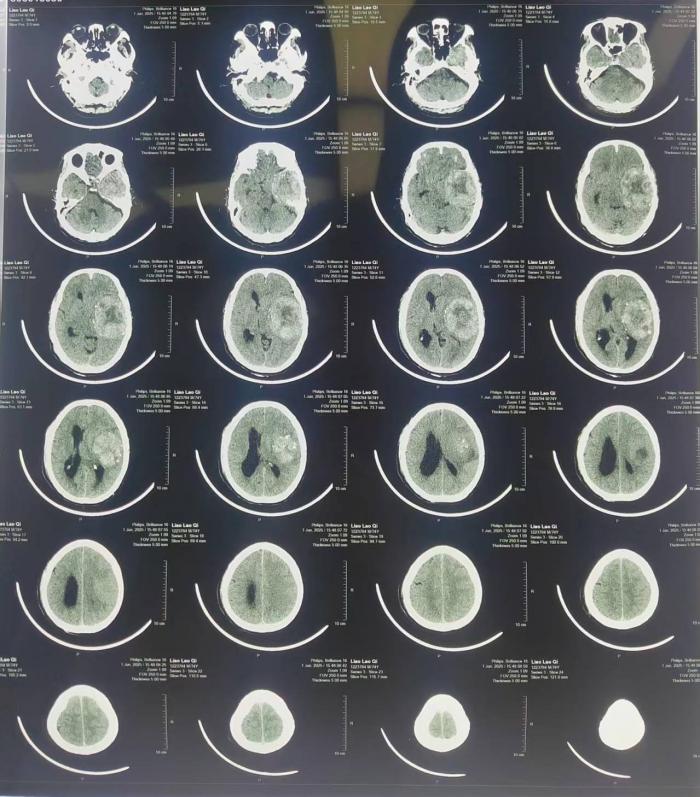

本网讯(通讯员 唐维豪)近日,湘南学院附属医院神经外科与麻醉科上演“生命接力”,成功为一名74岁高龄、合并肝原位癌术后、双肾重度积水及脑动脉硬化等多重复杂病症的患者,实施颅内左颞叶7×6cm巨大脑膜瘤切除术。这场在“生命禁区”开展的高风险手术,通过多学科联合诊疗(MDT)机制与精准麻醉管理,成功化解脑疝危机,彰显了医院在复杂危重症手术领域的综合救治实力。

老人因“颅内巨大占位继发脑疝”急诊入院,影像学检查显示肿瘤已压迫脑组织导致明显颅内压升高,随时面临呼吸骤停风险。面对患者高龄、多系统疾病叠加、手术耐受性极差的复杂状况,医院迅速召集神经外科、麻醉科、肿瘤科、放射科专家开展 MDT 会诊。经缜密评估,制定“个体化手术方案+脑保护型精准麻醉”的双重保障策略,为手术全程搭建“生命安全网”。

术前,在麻醉科主任李扬帆团队的带领下,针对患者高龄、基础疾病复杂、颅内压临界升高的特殊情况,制定了多模态精准监测方案:一方面,通过有创动脉压与中心静脉压实时监测构建循环“数字导航”系统,以0.1mmHg的调控精度动态维持血流动力学稳定;另一方面采用控制性降压技术精准平衡颅内压与脑灌注压,通过多参数联动调控避免脑缺血与脑水肿风险。历经6小时多学科紧密协作,直径7×6cm的巨大肿瘤被完整切除,患者术后即刻恢复自主呼吸,神经功能评估显示认知与肢体活动正常。